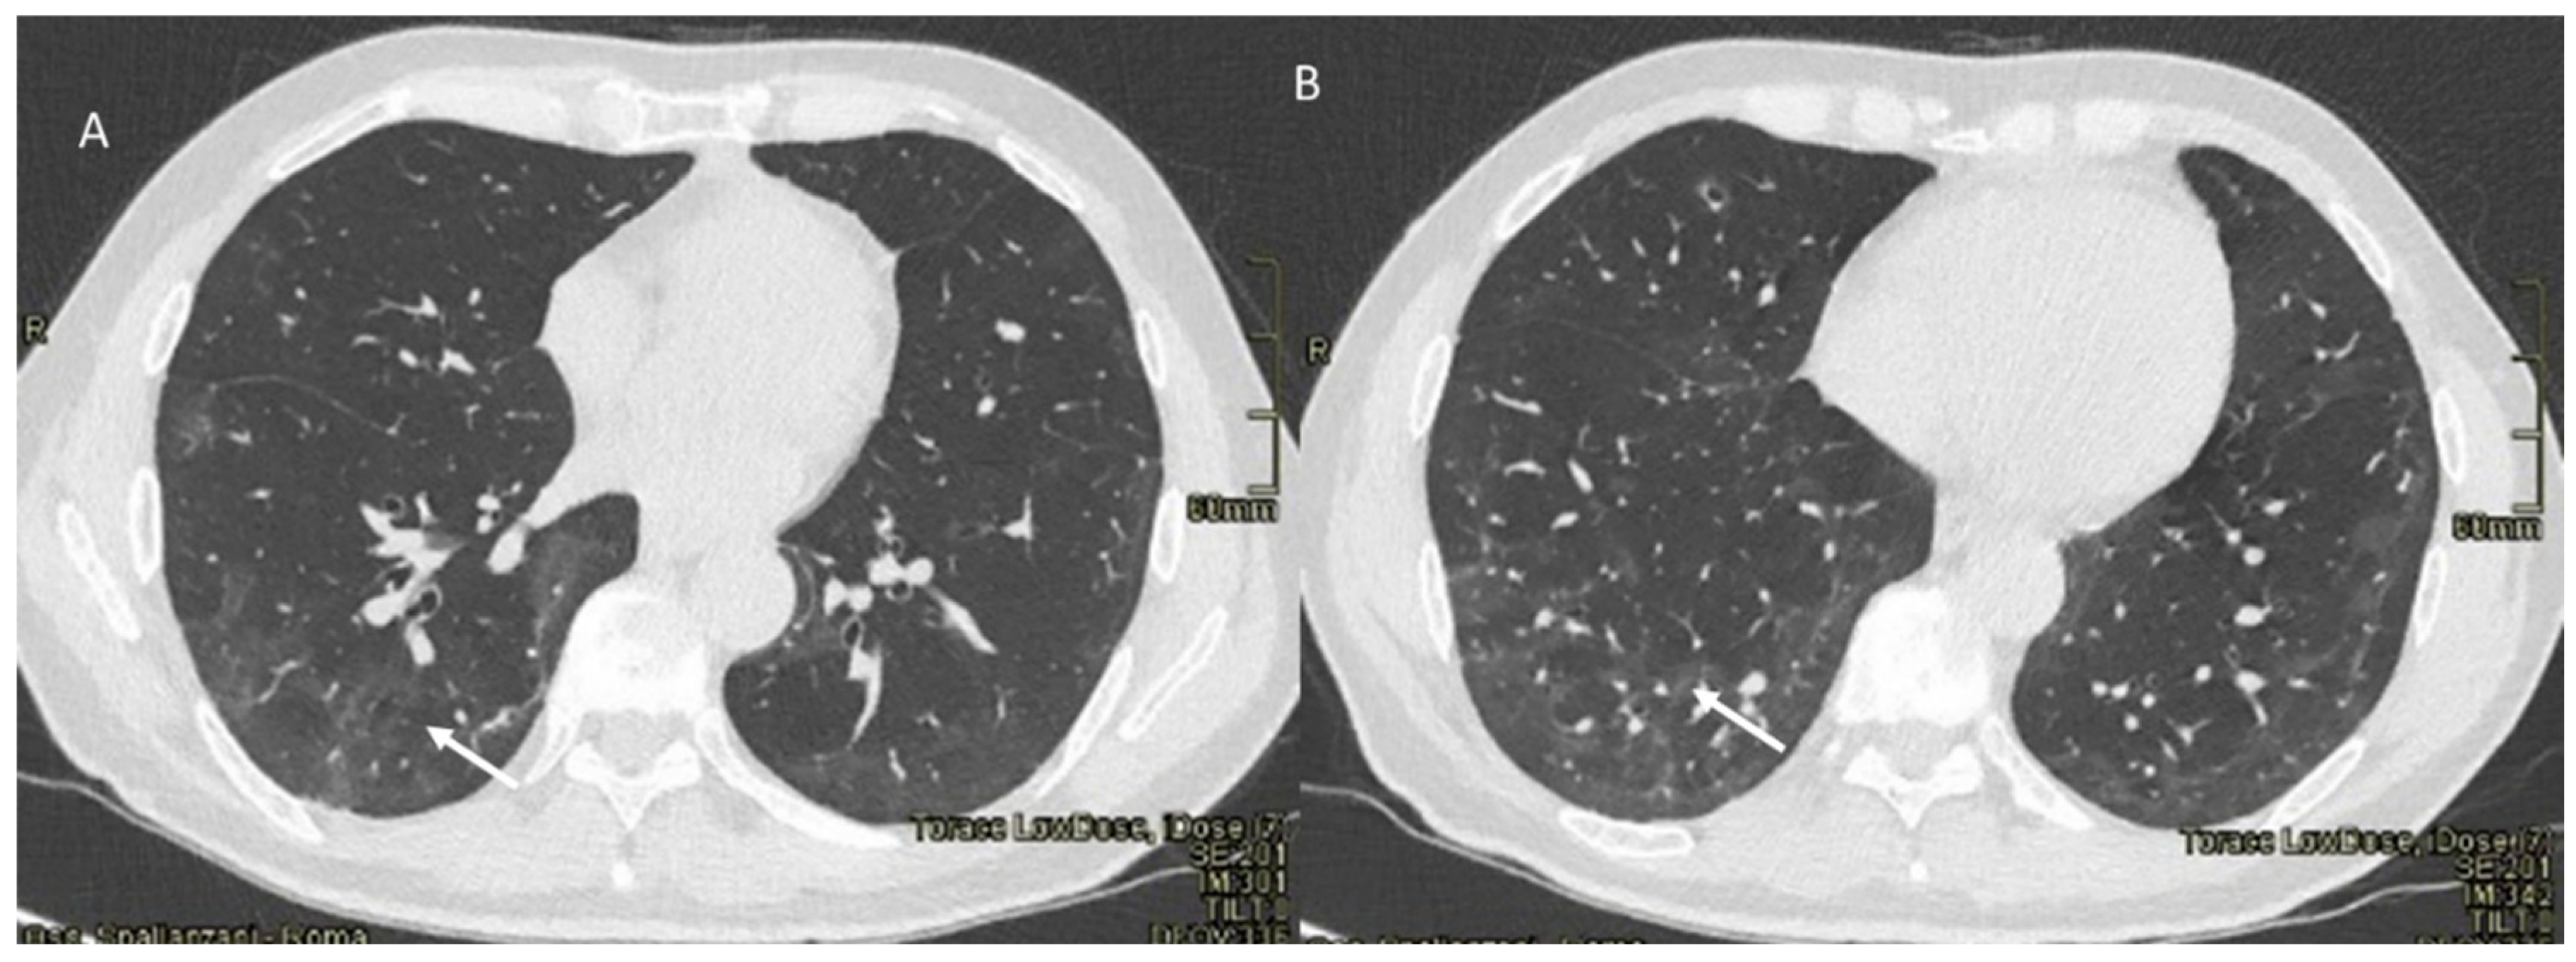

Immune checkpoint inhibitor (ICI)-related pneumonia could cause significant morbidity, with possible discontinuation of therapy and possible mortality [118]. The time to onset of pneumonia ranges from 9 days to over 19 months after the initiation of therapy, with a median time of 2.8 months [118]. Imaging plays a crucial role in this effect detection. Although X-ray may be an initial tool, CT is able to detect all subtle changes in pneumonitis and help to differentiate among subtypes, as described by Delaunay et al. [122]. Investigations described 64 cases of pneumonia with the following CT patterns: (a) organized pneumonia (OP) (23%), (b) hypersensitivity pneumonitis (HP) (16%), (c) non-specific interstitial pneumonia (NSIP) (8%) and (d) bronchiolitis (6%). Some patients were diagnosed with concomitant patterns and a distinctive pattern was not identified in 36% of cases [122]. OP’s pattern usually shows bilateral peribronchovascular and subpleural ground-glass and airspace opacities, with mid- to lower-lung predominance (Figure 2).

Figure 2. ICI-related pneumonitis. OP pattern on CT (axial: (A) and coronal: (B)): ground-glass and airspace opacities (arrows).